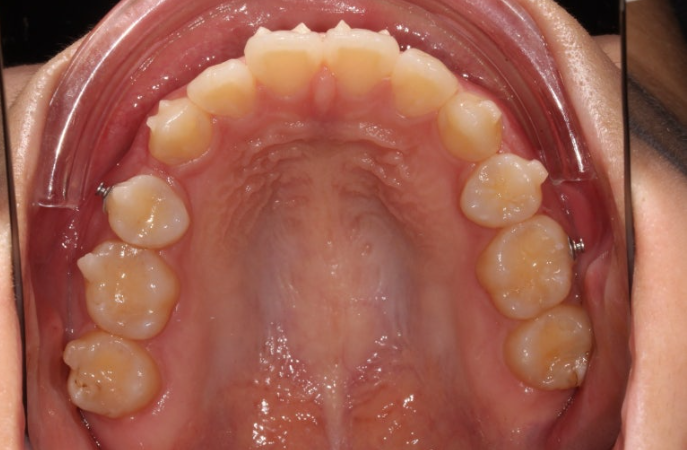

24.03

5개월에 걸친 부분교정으로 이제 겨우 어금니가 섰으니 재제작을 준비해야죠.

첫 추가장치 제작에 들어갔고 24년 4월부터 12월까지, 34개 추가장치를 모두 낀 후 모습입니다.

발치공간은 어금니 쓰러짐 없이 잘 닫혔고

양측 교합은 모두 좋습니다.